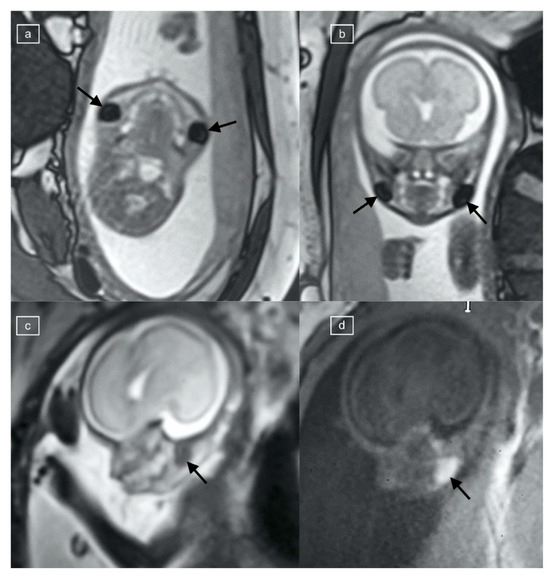

Figure 3.

(a,b) Comparison of TRUFI and HASTE MRI appearances of the fetal buccal fat pad in a 25-week fetus with congenital diaphragmatic hernia. (a) Coronal TRUFI demonstrates the oval low-signal-intensity fat pad on the right (arrow), which is isointense to soft tissue on the HASTE image (b).

Figure 4.

(a,b) Echo planar imaging at TE42 demonstrates low signal buccal fat pads in this 28-week gestational age fetus with diaphragmatic hernia (arrows).